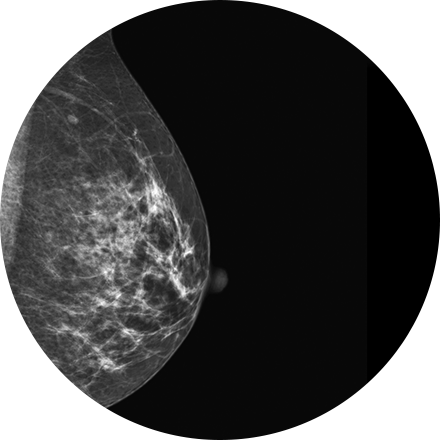

What is Digital Mammography?

Digital Mammography is a type of low-dose X-ray of the breast. It reveals masses and micro-calcifications within and around the breast that may indicate breast problems including, but not just limited to cancer.